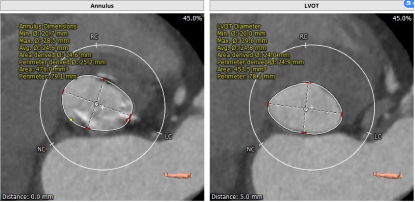

主动脉CT

本病例窦部情况可,瓣环周长24mm左右,判断使用VitaFlow24或VitaFlow27号瓣膜。